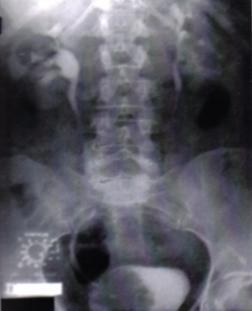

Fig.8 Imagini lacunare in aria vezicii urinare sugerand tumori vezicale superficiale [51].